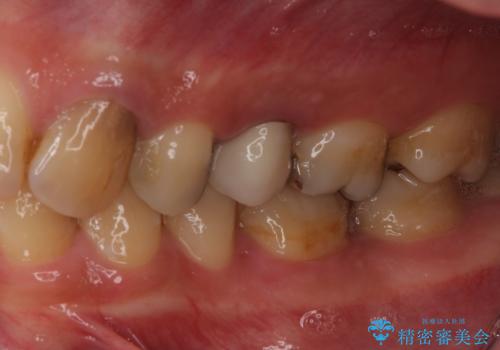

ご来院当初、患者様は1番奥歯のセラミック治療をご希望されてました。しかし、しっかり診査をして1本手前の歯を治療した方が良いとご提案させて頂きました。

また、奥歯が虫歯になりやすい原因として夜間の歯ぎしりで、歯に小さいヒビが入っている疑いがありました。就寝時マウスピースを使用して予防して頂くこともご提案し、患者様には大変満足して頂きました。